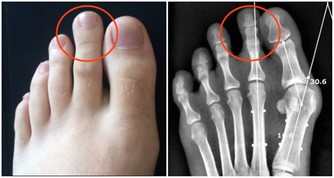

牙齒鬆動,牙齦萎縮都是骨質疏鬆症的徵兆。

根據相關專家的一項研究,患有骨質疏鬆症的患者比沒有患這種疾病的患者更容易掉牙。

牙科的x光片可以作為骨質疏鬆症的篩查工具,

研究表明牙科x光片與正常骨密度的人相比,可以鑑別是否患有骨質疏鬆症。